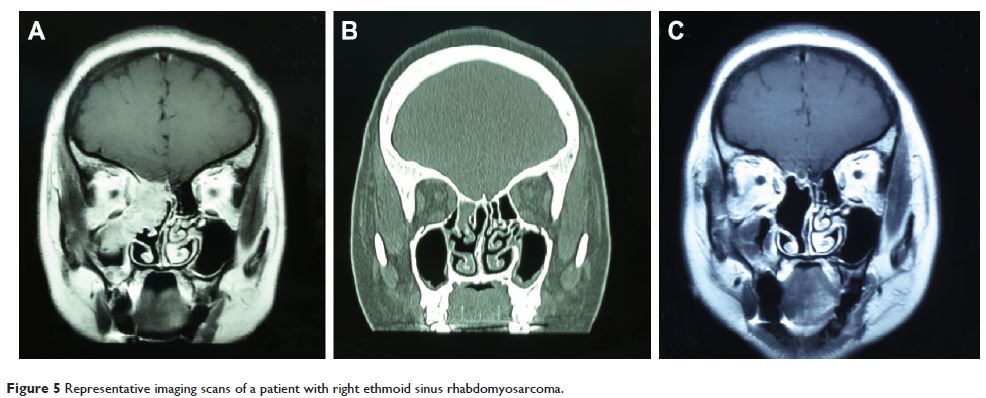

Original Research 视频

鼻内镜微创手术切除鼻腔鼻窦恶性肿瘤的疗效和复发的危险因素分析

- 作者:何宁,陈晓红,张罗,陈学军,黄志刚,钟琦,马泓智,冯凌,侯丽珍,房居高

- 期刊:Therapeutics and Clinical Risk Management